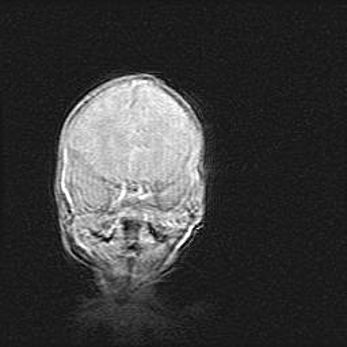

Сообщающаяся гидроцефалия. Кистозная энцефаломаляция головного мозга.

Возраст: 3 месяца 4 дня

Вес: 3100 г

Пол: женский

Окружность головы: 34 см

Срок гестации: 31 неделя

Кистозная энцефаломаляция головного мозга - одна из форм поражения головного мозга в детском возрасте. Характеризуется возникновением множественных и распространённых кист в коре, белом веществе и подкорковых образованиях головного мозга у плодов, новорождённых и детей раннего возраста. Развитие кистозной энцефаломаляции связано с внутриутробной асфиксией и гипотонией, родовой травмой, тромбозом синусов, пороками развития сосудов, инфекциями, сепсисом и другими причинами. Наиболее значимые инфекционные агенты: вирусы простого герпеса, цитомегалии, краснухи, токсоплазмы, энтеробактерии, золотистый стафилококк и другие.